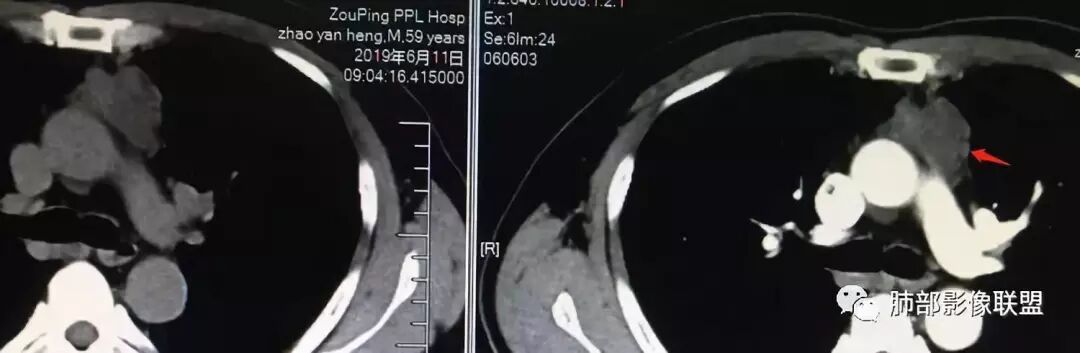

男,59

2015年小,2019年增强,不规则强化不均匀。

48-60-70,28-30-24,不规则渐进性强化,密度不均。

南边:

边缘张力不高

19 年

根据强化,高的70HU,低的没测,考虑囊实性

实性部分明显强

偏一侧

上面来的血供,病灶深分叶

附近心包似乎也不干净

有淋巴结